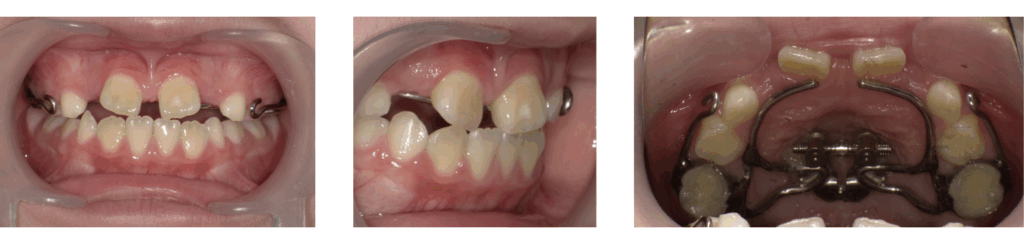

症例2:急速拡大装置のみ使用した症例

| 年齢 | 11歳 |

| 性別 | 男子 |

| 治療の理由(主訴) | ガタガタの見た目を治したい。 目立つのでワイヤー装置は付けたくない。 |

| 治療方法 | 顎顔面矯正 |

| 治療期間 | 1年4か月 |

| 費用 | 44万円 |

治療前

装置装着

拡大完了

治療後